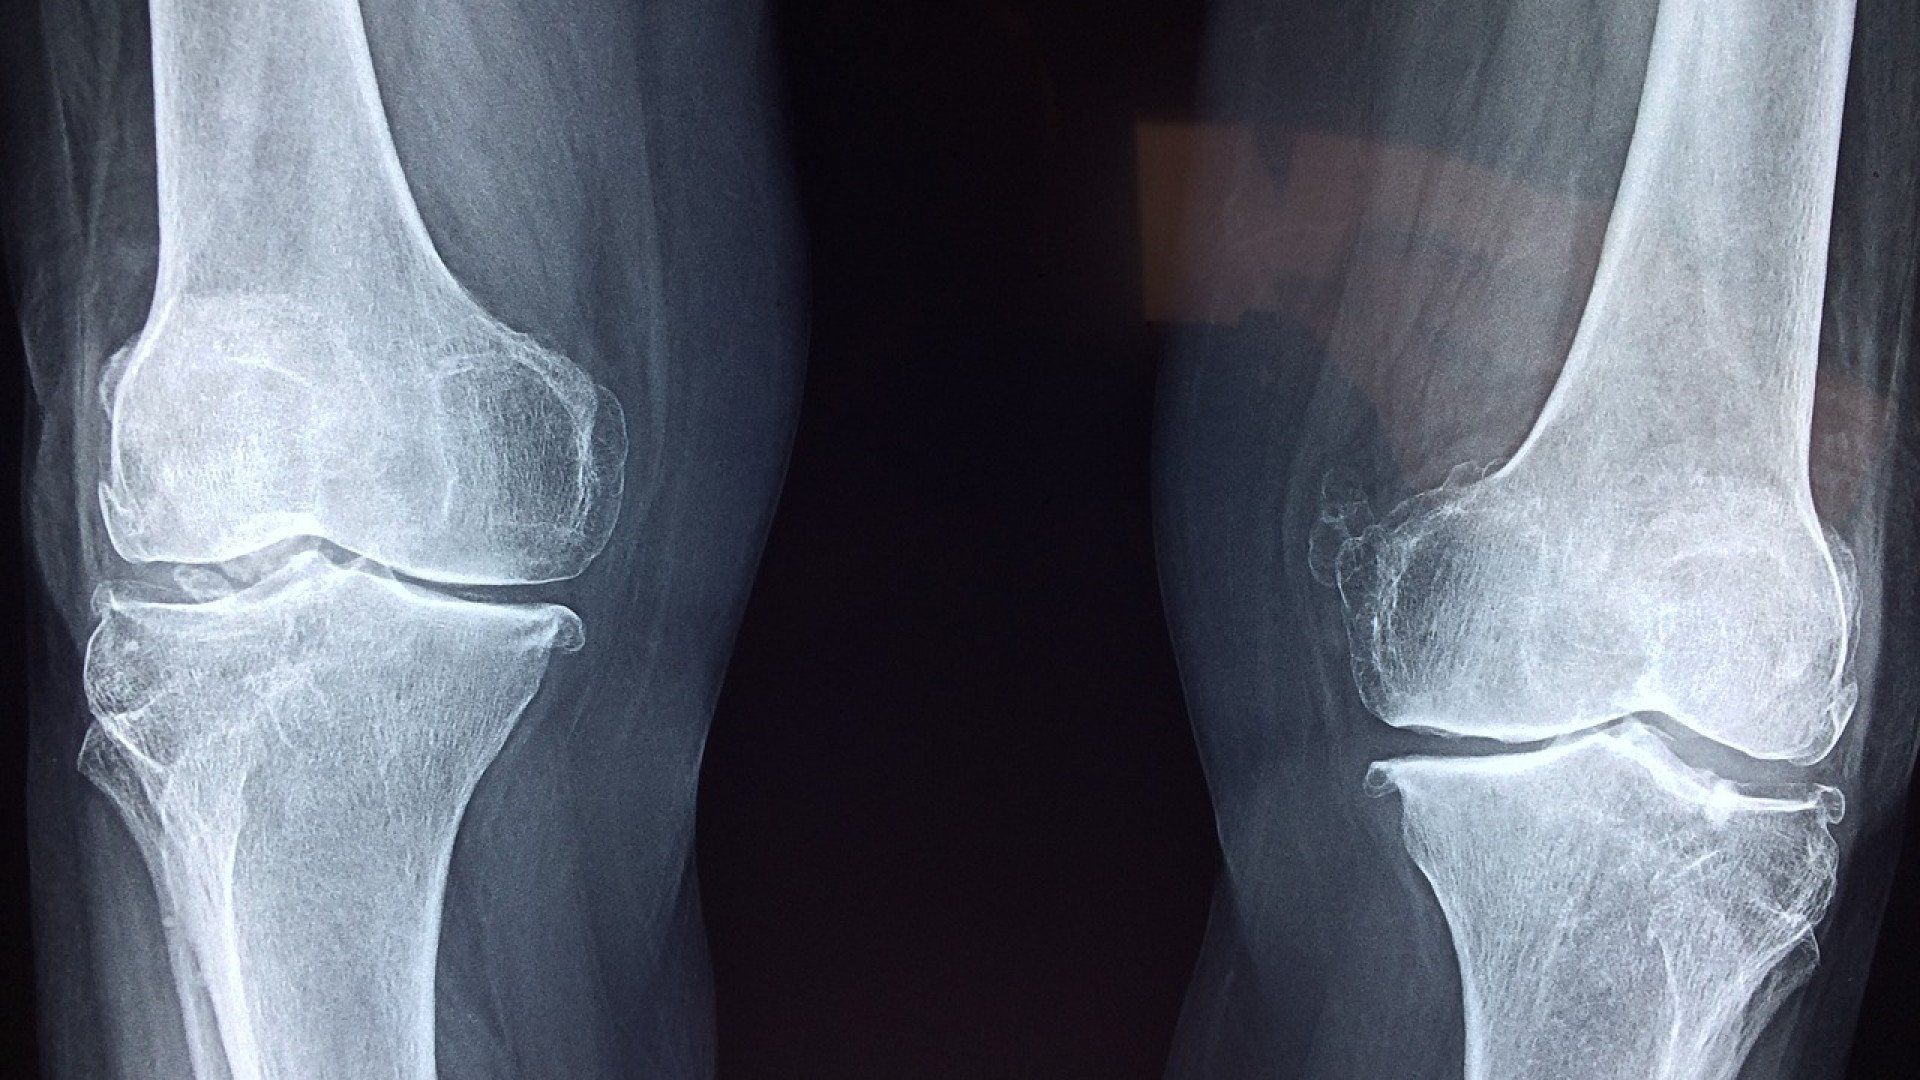

Les extrémités osseuses peuvent s’épaissir et former des ostéophytes, les fameux « becs de perroquet » visibles sur les radiographies.

Il faut garder à l’esprit qu’il n’existe pas forcément de liens entre l’importance des lésions visibles sur les clichés radiographiques et vos douleurs. C’est-à-dire qu’une arthrose « sévère » sur les radios peut ne pas être douloureuse et vous pouvez très bien ressentir des douleurs importantes alors que les radiographies ne montrent pas de dégâts importants.